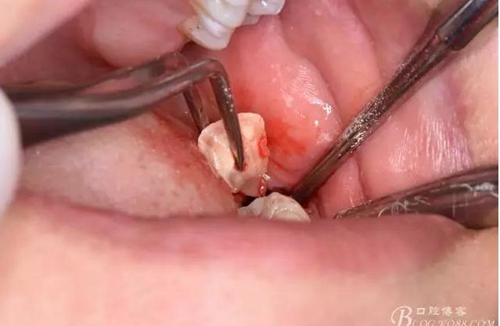

圖10.用丁字挺取出牙冠舌側(cè)部分

圖11.取出的38舌側(cè)部分

圖12.接著取出38的頰側(cè)部分牙冠